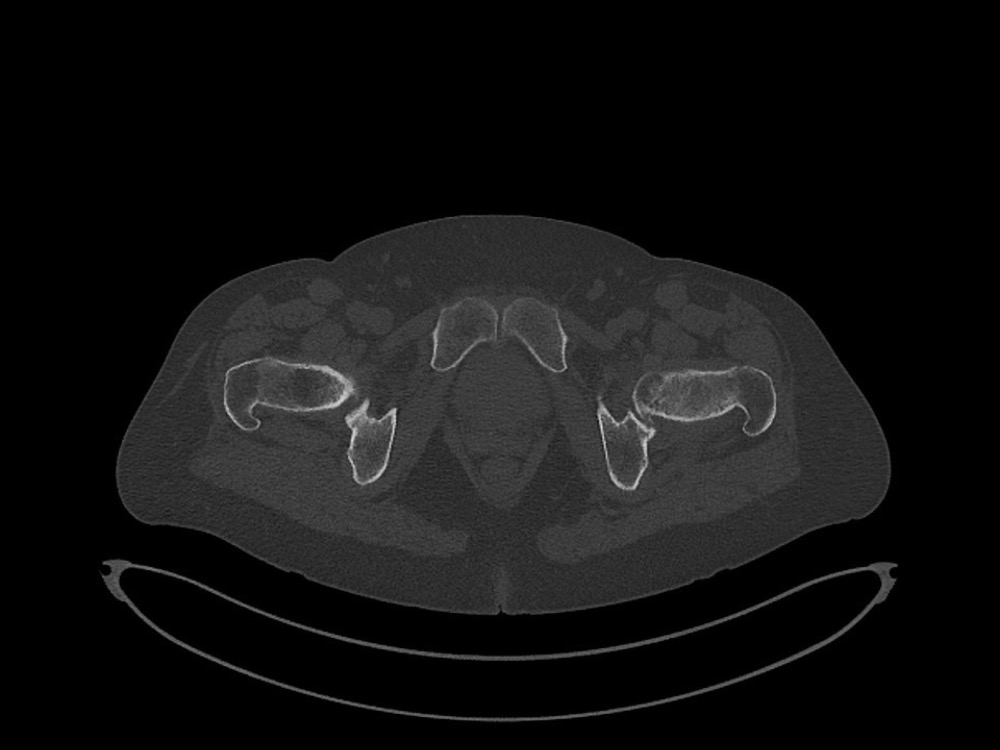

Douleurs de hanche

Linda Ouerd 06/11/2019